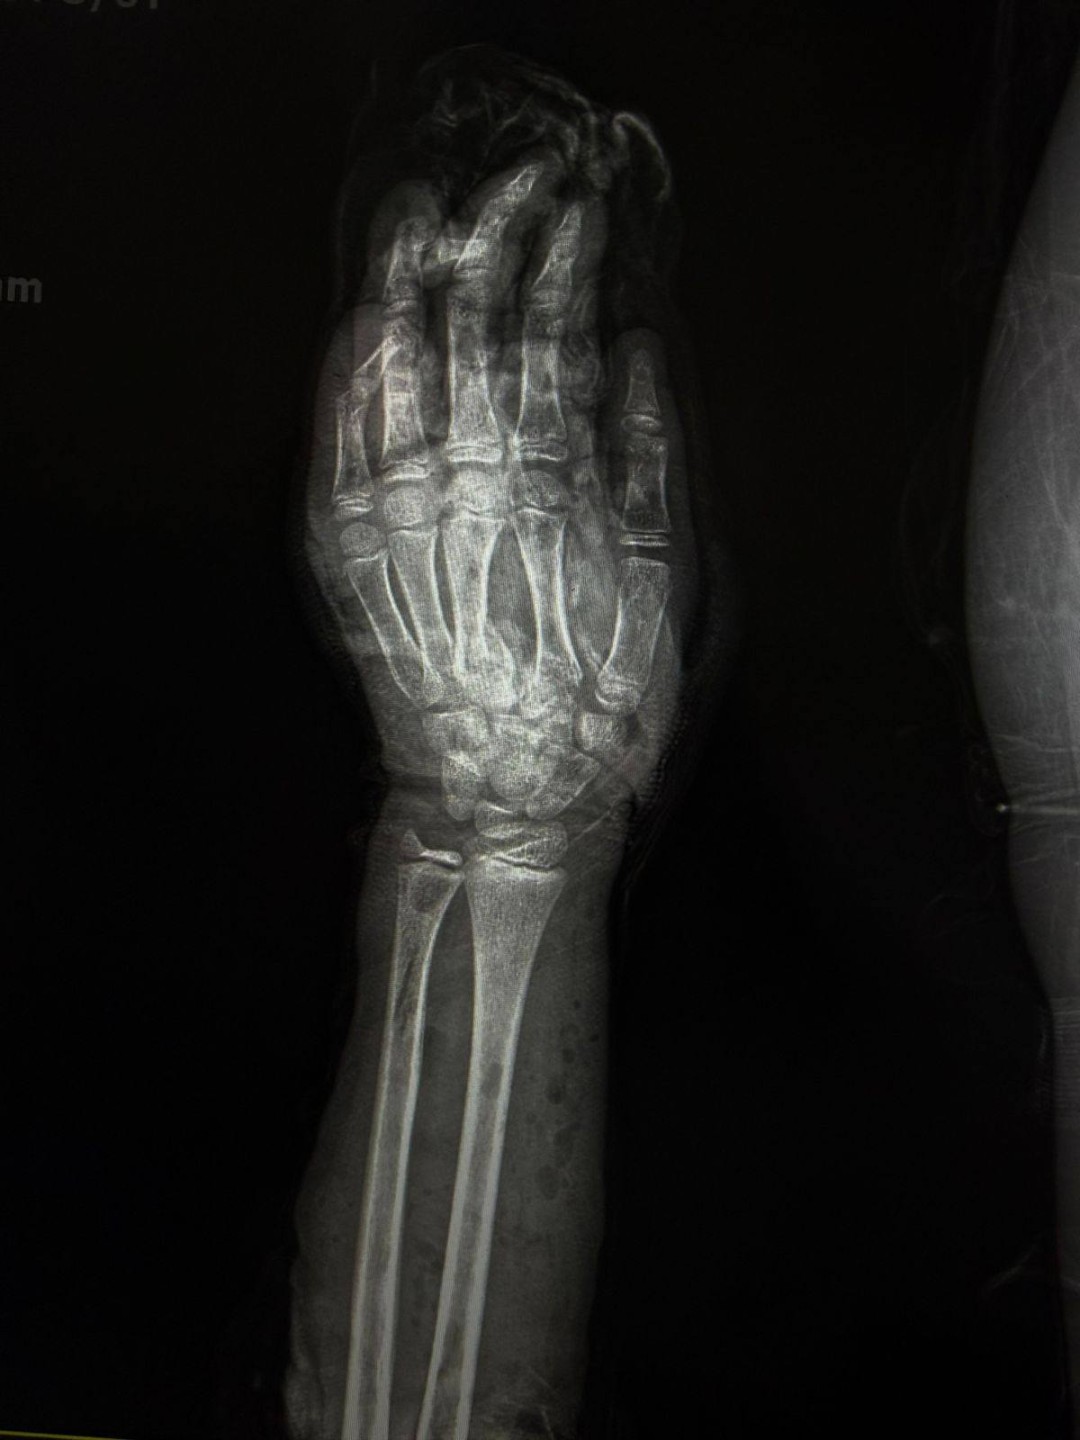

نجح فريق طبي متخصص بمستشفى الطوارئ الجديد بجامعة سوهاج، في إنقاذ ذراع طفل يبلغ من العمر 12 عامًا، عقب تعرضه لإصابة شديدة نتيجة حادث طاحونة قمح، أسفر عن تهتك كامل بأنسجة الذراع، وكسور متعددة بالأصابع، إلى جانب إصابة الأوتار والأعصاب.

وأشار الدكتور أحمد كمال، المدير التنفيذي للمستشفيات الجامعية ، إلى أن فريق وحدة جراحات اليد الميكروسكوبية قام بتثبيت الكسور الدقيقة بالأصابع، وتوصيل الأوتار والأعصاب المصابة، مع استكشاف الأوعية الدموية والتأكد من سلامتها، فيما تولى فريق جراحة التجميل إجراء رقعة جلدية لتعويض الجزء المتهتك المفقود من الذراع.